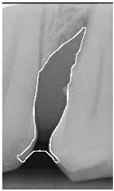

2.3.6. Extract Closed Area and Filling

To ensure that only the area framing the symptom is preserved, and to remove the rest of the interfering areas or lines, the symptom frames are extracted according to the closure algorithm, i.e., the maximum connectivity area can be preserved to remove the frames of the non-symptomatic areas, as shown in Figure 7b. After the closure process, some of the frame lines are less smooth than others, which may affect the discrimination accuracy. To deal with this situation, this study performs the filling of the frame lines at the symptom area to facilitate the training of the model. Black and white are chosen to highlight the contrast and to compare the difference in discrimination between the two fill colors, as shown in Figure 7c,d.

Figure 7. Comparison of extracting the closed area and filling. (a) Close operation. (b) Extracting the closed area. (c) Filling with white. (d) Filling with black.